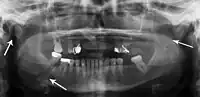

Panoramic radiograph of a simple mandible fracture of the right mandibular body, minimally displaced. Note that the teeth to the left of the fracture do not touch -

lateral oblique image demonstrating a fractured mandible.